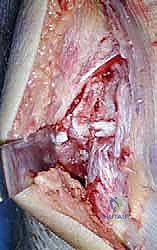

2. الشق الجراحي وحماية الأعصاب

يقوم الدكتور هطيف بعمل شق طولي خلف الكوع. الخطوة الأكثر أهمية هنا هي تحديد العصب الزندي (Ulnar Nerve) وعزله وحمايته بعناية فائقة باستخدام تقنيات الجراحة الميكروسكوبية الدقيقة لتجنب أي تلف قد يؤدي إلى ضعف في اليد.